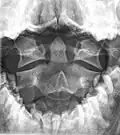

A fracture of the base of the dens as seen on plain X-ray -

Axis on X-ray taken through an open mouth, teeth visible -